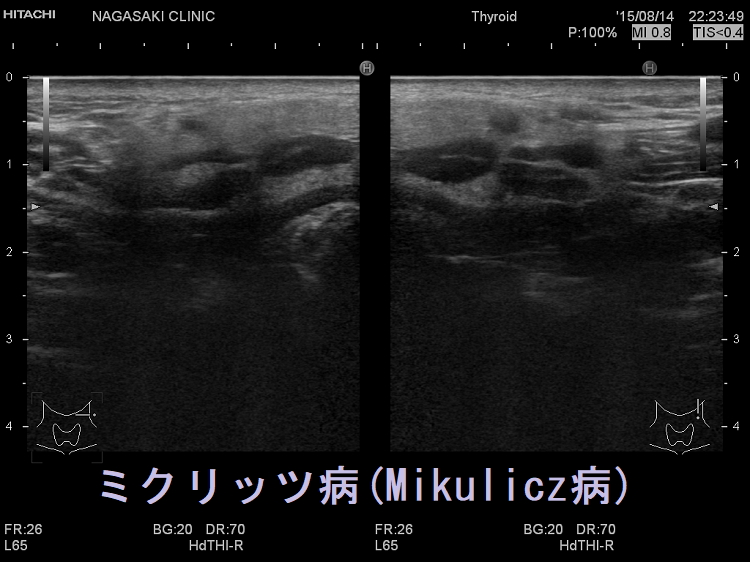

ミクリッツ病(Mikulicz病、IgG4唾液腺炎、IgG4関連硬化性唾液腺炎)はシェーグレン症候群と非常に類似しているが、シェーグレン症候群に特異的な抗SS-A抗体/抗SS-B抗体はほとんど陰性です。

ミクリッツ病にIgG4関連甲状腺炎を合併した報告があります。[Eye Sci. 2014 Mar;29(1):47-52.]